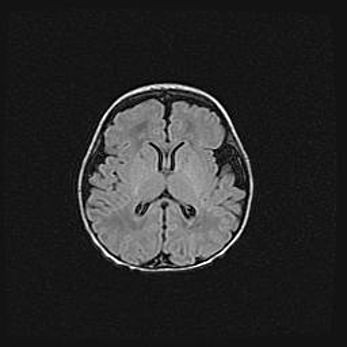

Сообщающаяся гидроцефалия. Кистозная энцефаломаляция головного мозга.

Возраст: 3 месяца 4 дня

Вес: 3100 г

Пол: женский

Окружность головы: 34 см

Срок гестации: 31 неделя

Кистозная энцефаломаляция головного мозга - одна из форм поражения головного мозга в детском возрасте. Характеризуется возникновением множественных и распространённых кист в коре, белом веществе и подкорковых образованиях головного мозга у плодов, новорождённых и детей раннего возраста. Развитие кистозной энцефаломаляции связано с внутриутробной асфиксией и гипотонией, родовой травмой, тромбозом синусов, пороками развития сосудов, инфекциями, сепсисом и другими причинами. Наиболее значимые инфекционные агенты: вирусы простого герпеса, цитомегалии, краснухи, токсоплазмы, энтеробактерии, золотистый стафилококк и другие.